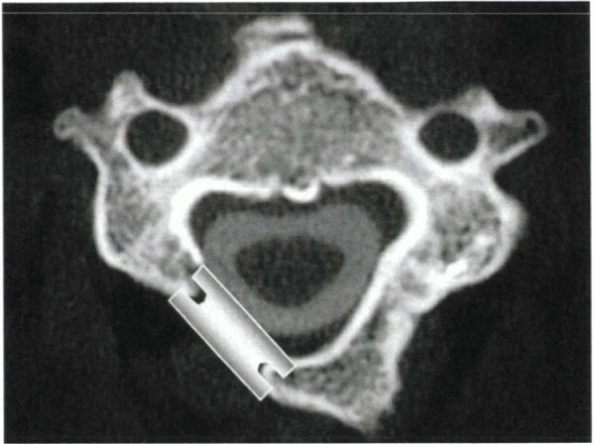

Figure 26-4 The vertebral artery (black arrow)

typically lies in the anterior two thirds of the disc space. It is ventral to the usual location of nerve root compression (i.e., at the level of the posterior uncinate [white arrowhead]). The lateral border of the uncinate marks the lateral safe zone (black line). To decompress the nerve root laterally in the foramen (white arrow), while avoiding injury to the vertebral artery, the trajectory of decompression should course laterally in the posterior aspect of the disc space (dotted line). |